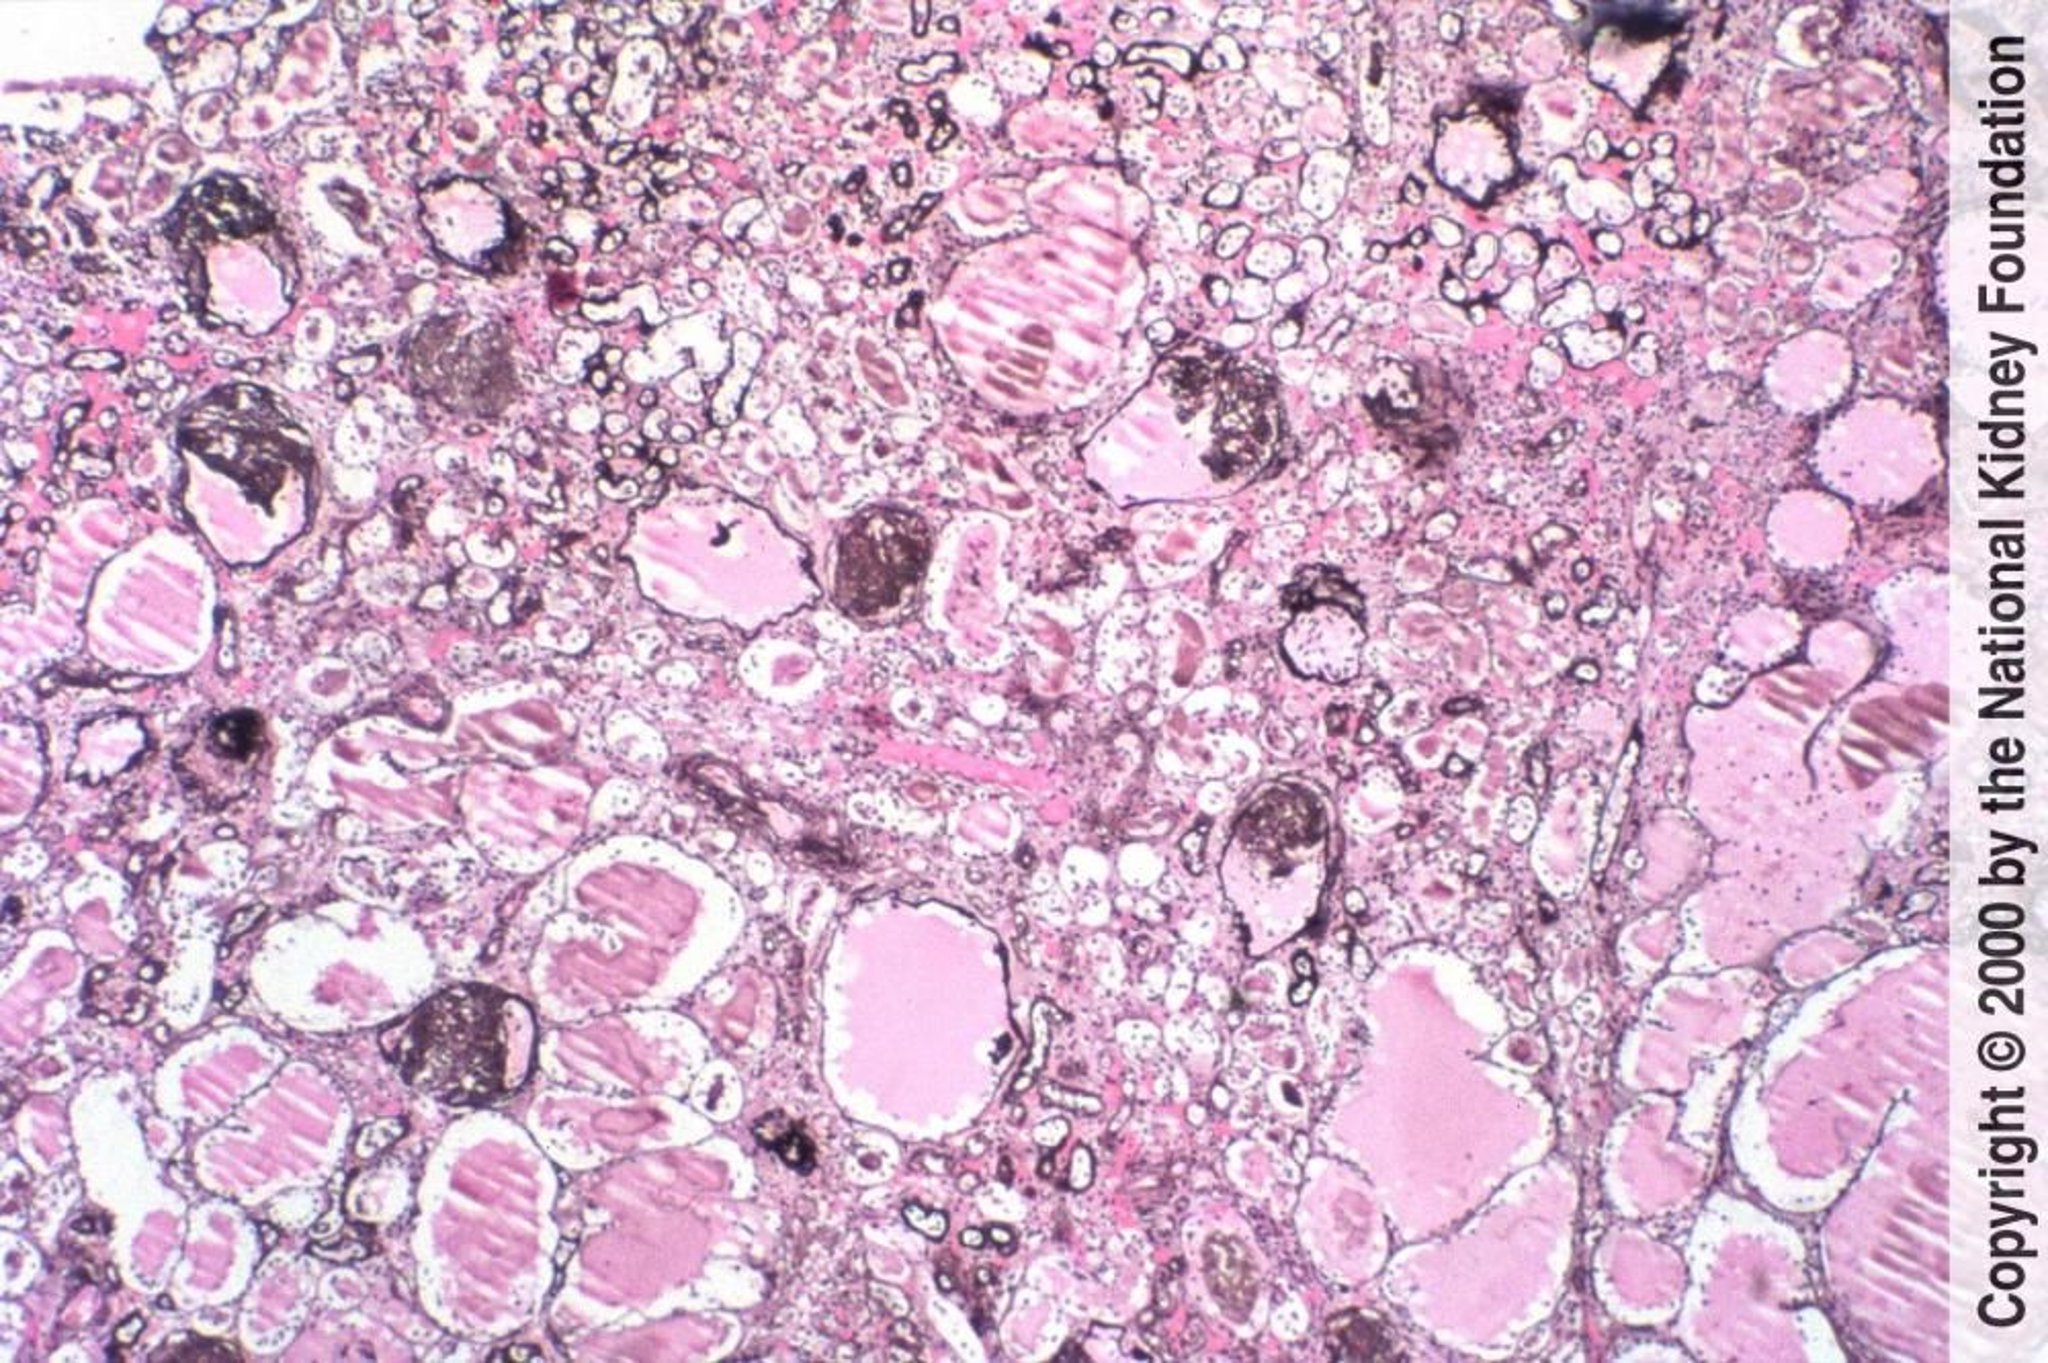

Nefropatia associada ao HIV (glomerulopatia colapsante)

A glomerulosclerose segmentar e focal com colapso dos tufos glomerulares e alterações tubulares microcísticas é típica da nefropatia associada ao HIV (coloração prata de Jones, × 100).

Image provided by Agnes Fogo, MD, and the American Journal of Kidney Diseases' Atlas of Renal Pathology (see www.ajkd.org).